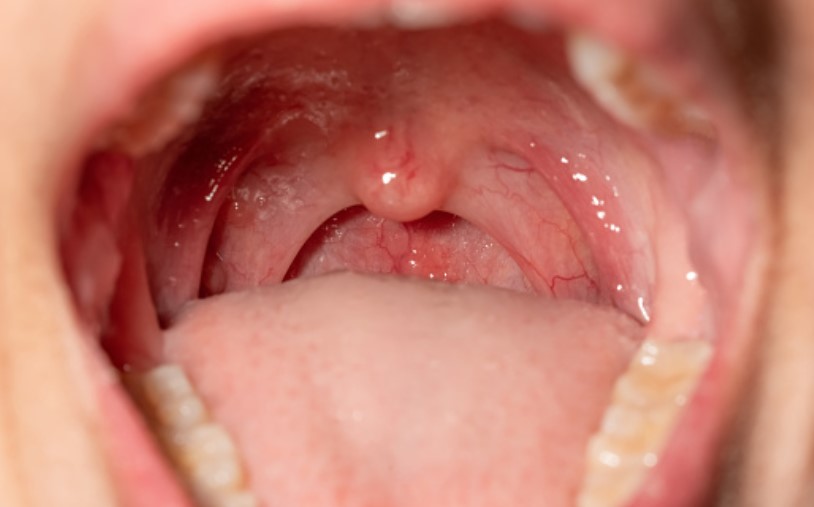

03. 혀가 두껍거나 목젖이 긴 경우, 구조적인 문제로 인해 발생하기도 합니다. 이로 인해 기도를 좁게 해서 코골이나 수면무호흡이 발생됩니다.

무호흡증 수술의 경우 환자의 기도 구조에 따라서 수술 결과가 좋은 환자가 있고 나쁜 환자가 있습니다. 예후가 좋은 수술환자의 경우는 편도가 크고 인후두벽이 잘 보이는 경우입니다. (Friedman staging) 이 밖에도 수면내시경 검사 등이 있어서 상황에 따라 종합적인 판단 하에 진행이 됩니다.

수면 무호흡증 수술 중 구개수구개인두성형술 이 있습니다. 편도선 포함해서 목젖을 잘라내는 수술입니다. 이 수술의 경우 세계적으로 성공률이 40% 입니다. 따라서 다양한 방법의 수술을 종합해서 진행하기도 합니다.